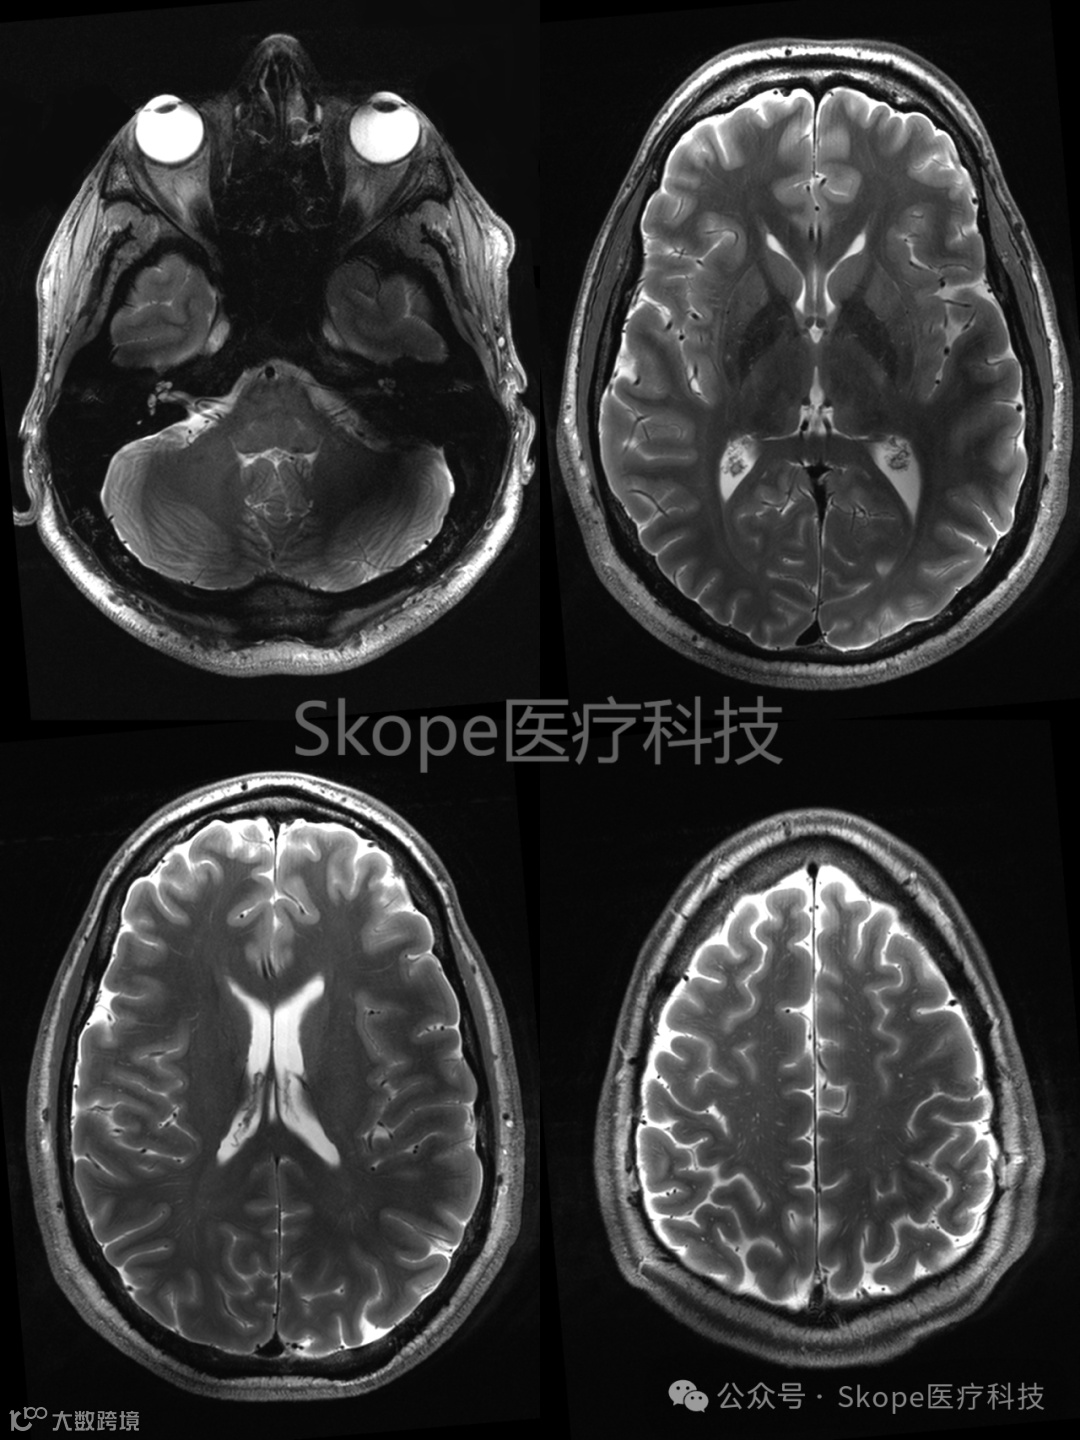

T2 Turbo Spin Echo 成像

来源:Skope

采集参数

视场:230 x 173 毫米

层厚:39

平面分辨率:0.2 x 0.2 毫米

层厚:3 毫米

加速因子 PE:2

采集时间:3:38

CP模式